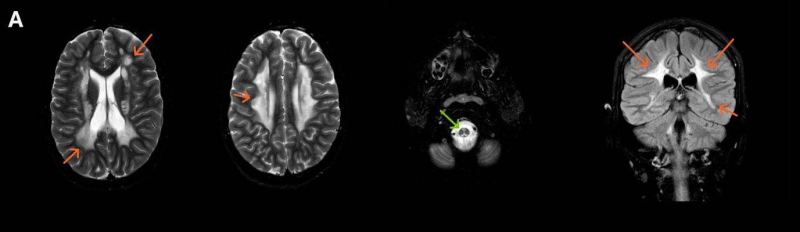

- A) Aksiyel T2A ve koronal T2A sekanslarda sentrum semiovale, korona radiata ve bazal ganglionlar düzeyinde bilateral frontoparietal derin periventriküler beyaz cevherde birleşme eğilimi gösteren hiperintens gliotik sinyal değişiklikleri (oklar) ve aksiyel T2A serilerde servikal spinal kordda posterior kolonda, lateral kesimlerde sinyal artımları (oklar) izlendi.

- B) Kontrastsız T1A serilerde tarifli alanlarda hipointens (oklar) görünüm izlendi. Kontrastlı T1A serilerde bu düzeyde (oklar) kontrastlanma artışı izlenmedi. Diffüzyon ağırlıklı serilerde belirgin diffüzyon kısıtlaması (oklar) görülmedi.

- LBSL, karakteristik radyolojik özelliklere sahiptir. MRG’de tipik olarak bilateral ve simetrik beyaz cevher sinyal değişiklikleri görülürken, subkortikal U lifleri, internal kapsülün posterior kolları, trigeminal sinir traktları, serebellum, korpus kallozumun spleniumu, medulla oblongata ve omurilikteki dorsal kolonlar ile lateral kortikospinal traktlar genellikle korunur.

- Etkilenen bölgelerde T1’de hipointens, T2/FLAIR’da hiperintens sinyal değişiklikleri izlenir. DWI’de lezyonların periferinde kısıtlı difüzyon görülebilir. MRS’de beyaz cevherde laktat artışı saptanabilir, ancak bu her hastada mevcut değildir.

- LBSL tanısında majör kriterler; subkortikal U lifleri korunmuş serebral beyaz cevher, servikal düzey dahil omurilik dorsal kolonları ve lateral kortikospinal traktlar, medulla oblongata piramitleri veya medial lemniskus dekusasyonu tutulumu iken; minör kriterler korpus kallozum spleniumu, internal kapsül posterior kolu, superior ve inferior serebellar pedinküller, trigeminal sinir traktları, mezensefalik trigeminal yollar, medulla oblongata anterior spinosebellar traktları ve serebellar beyaz cevherdeki sinyal değişiklikleridir.